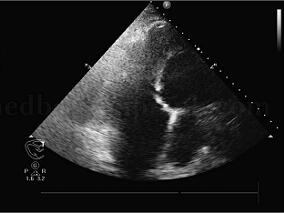

1小时条评论【病例1】 病史和相关检查 患者,女性,63岁,8小时前无诱因出现胸闷、心悸、胸痛,为压痛,伴后背痛,无大汗,含服硝酸酯类药物10分钟后疼痛缓解。心电图示:V1~V4导联ST段抬高,T波倒置。冠状动脉造影示:前降支近端限局80%狭窄,前降支远端30%~40%狭窄。 超声...